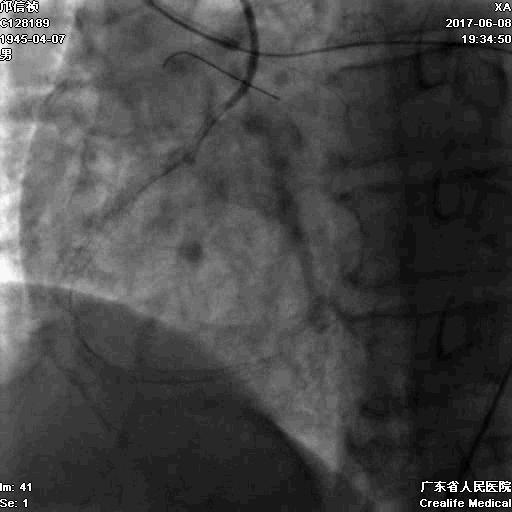

冠脉造影

基本资料

Syntax score 37.5

RCA闭塞段球囊扩张后IVUS

支架术后造影结果